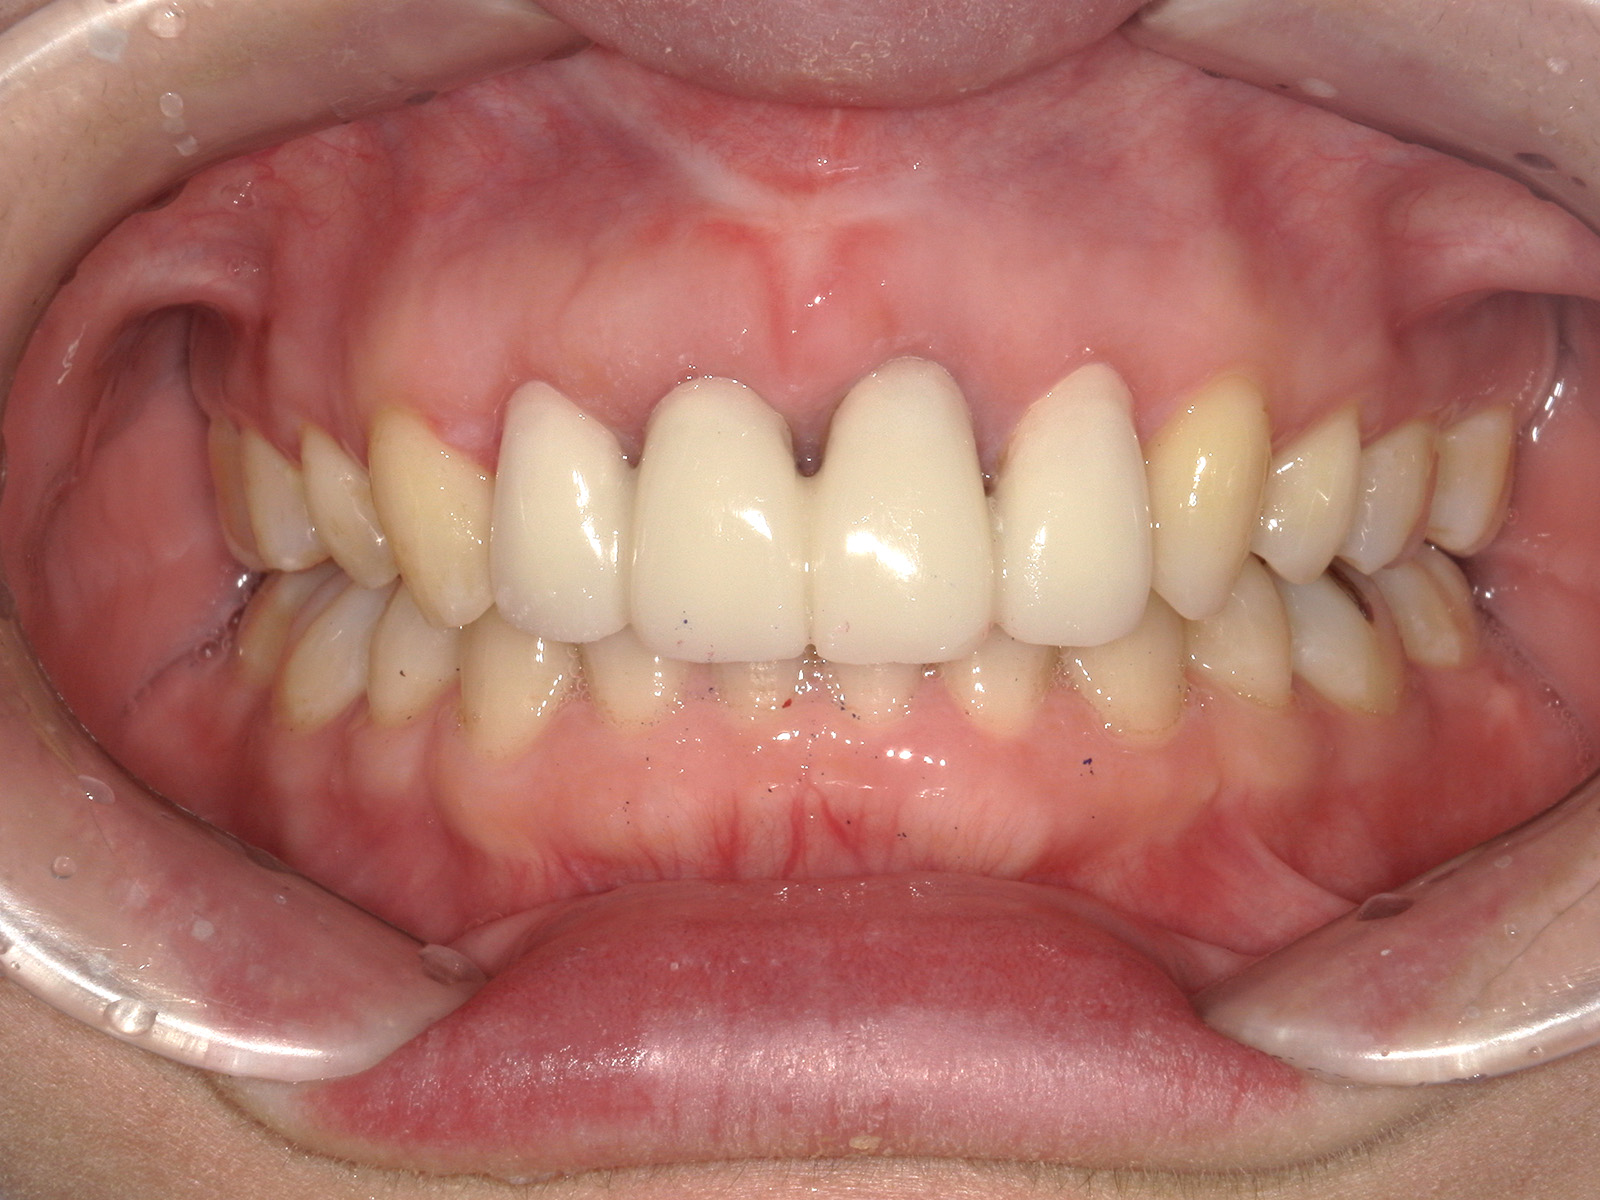

被せ物を装着し、治療完了。

歯茎や周囲の骨を丁寧に削り、歯の根を十分に露出させることで、被せ物を安定して装着できるようにします。

歯の保存を第一に考える治療の一つです。